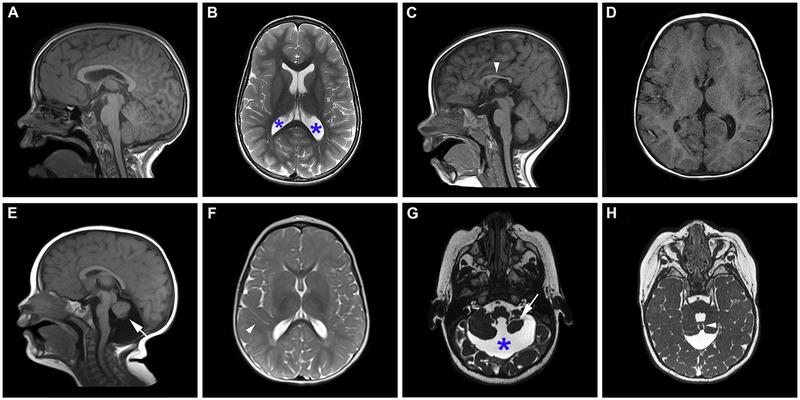

Intellectual disability (ID) and autism spectrum disorder (ASD) are genetically heterogeneous neurodevelopmental disorders. We sought to delineate the clinical, molecular, and neuroimaging spectrum of a novel neurodevelopmental disorder caused by variants in the zinc finger protein 292 gene (ZNF292).

智力障碍 (ID) 和自闭症谱系障碍 (ASD) 是遗传异质性的神经发育障碍。我们试图描绘由锌指蛋白 292 基因 (ZNF292) 变异引起的新型神经发育障碍的临床、分子和神经影像学谱。